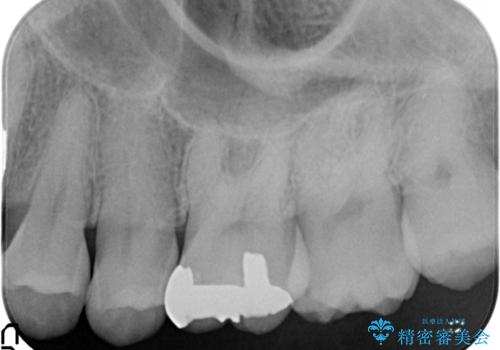

メタルフリー セラミックインレー

- メタルフリーの治療を希望されて来院されました。

セラミックインレーの治療を2回の来院で終了しております

e-max プレスインレーにて修復治療を行っているため適合性及び審美性の高い治療を行うことができます